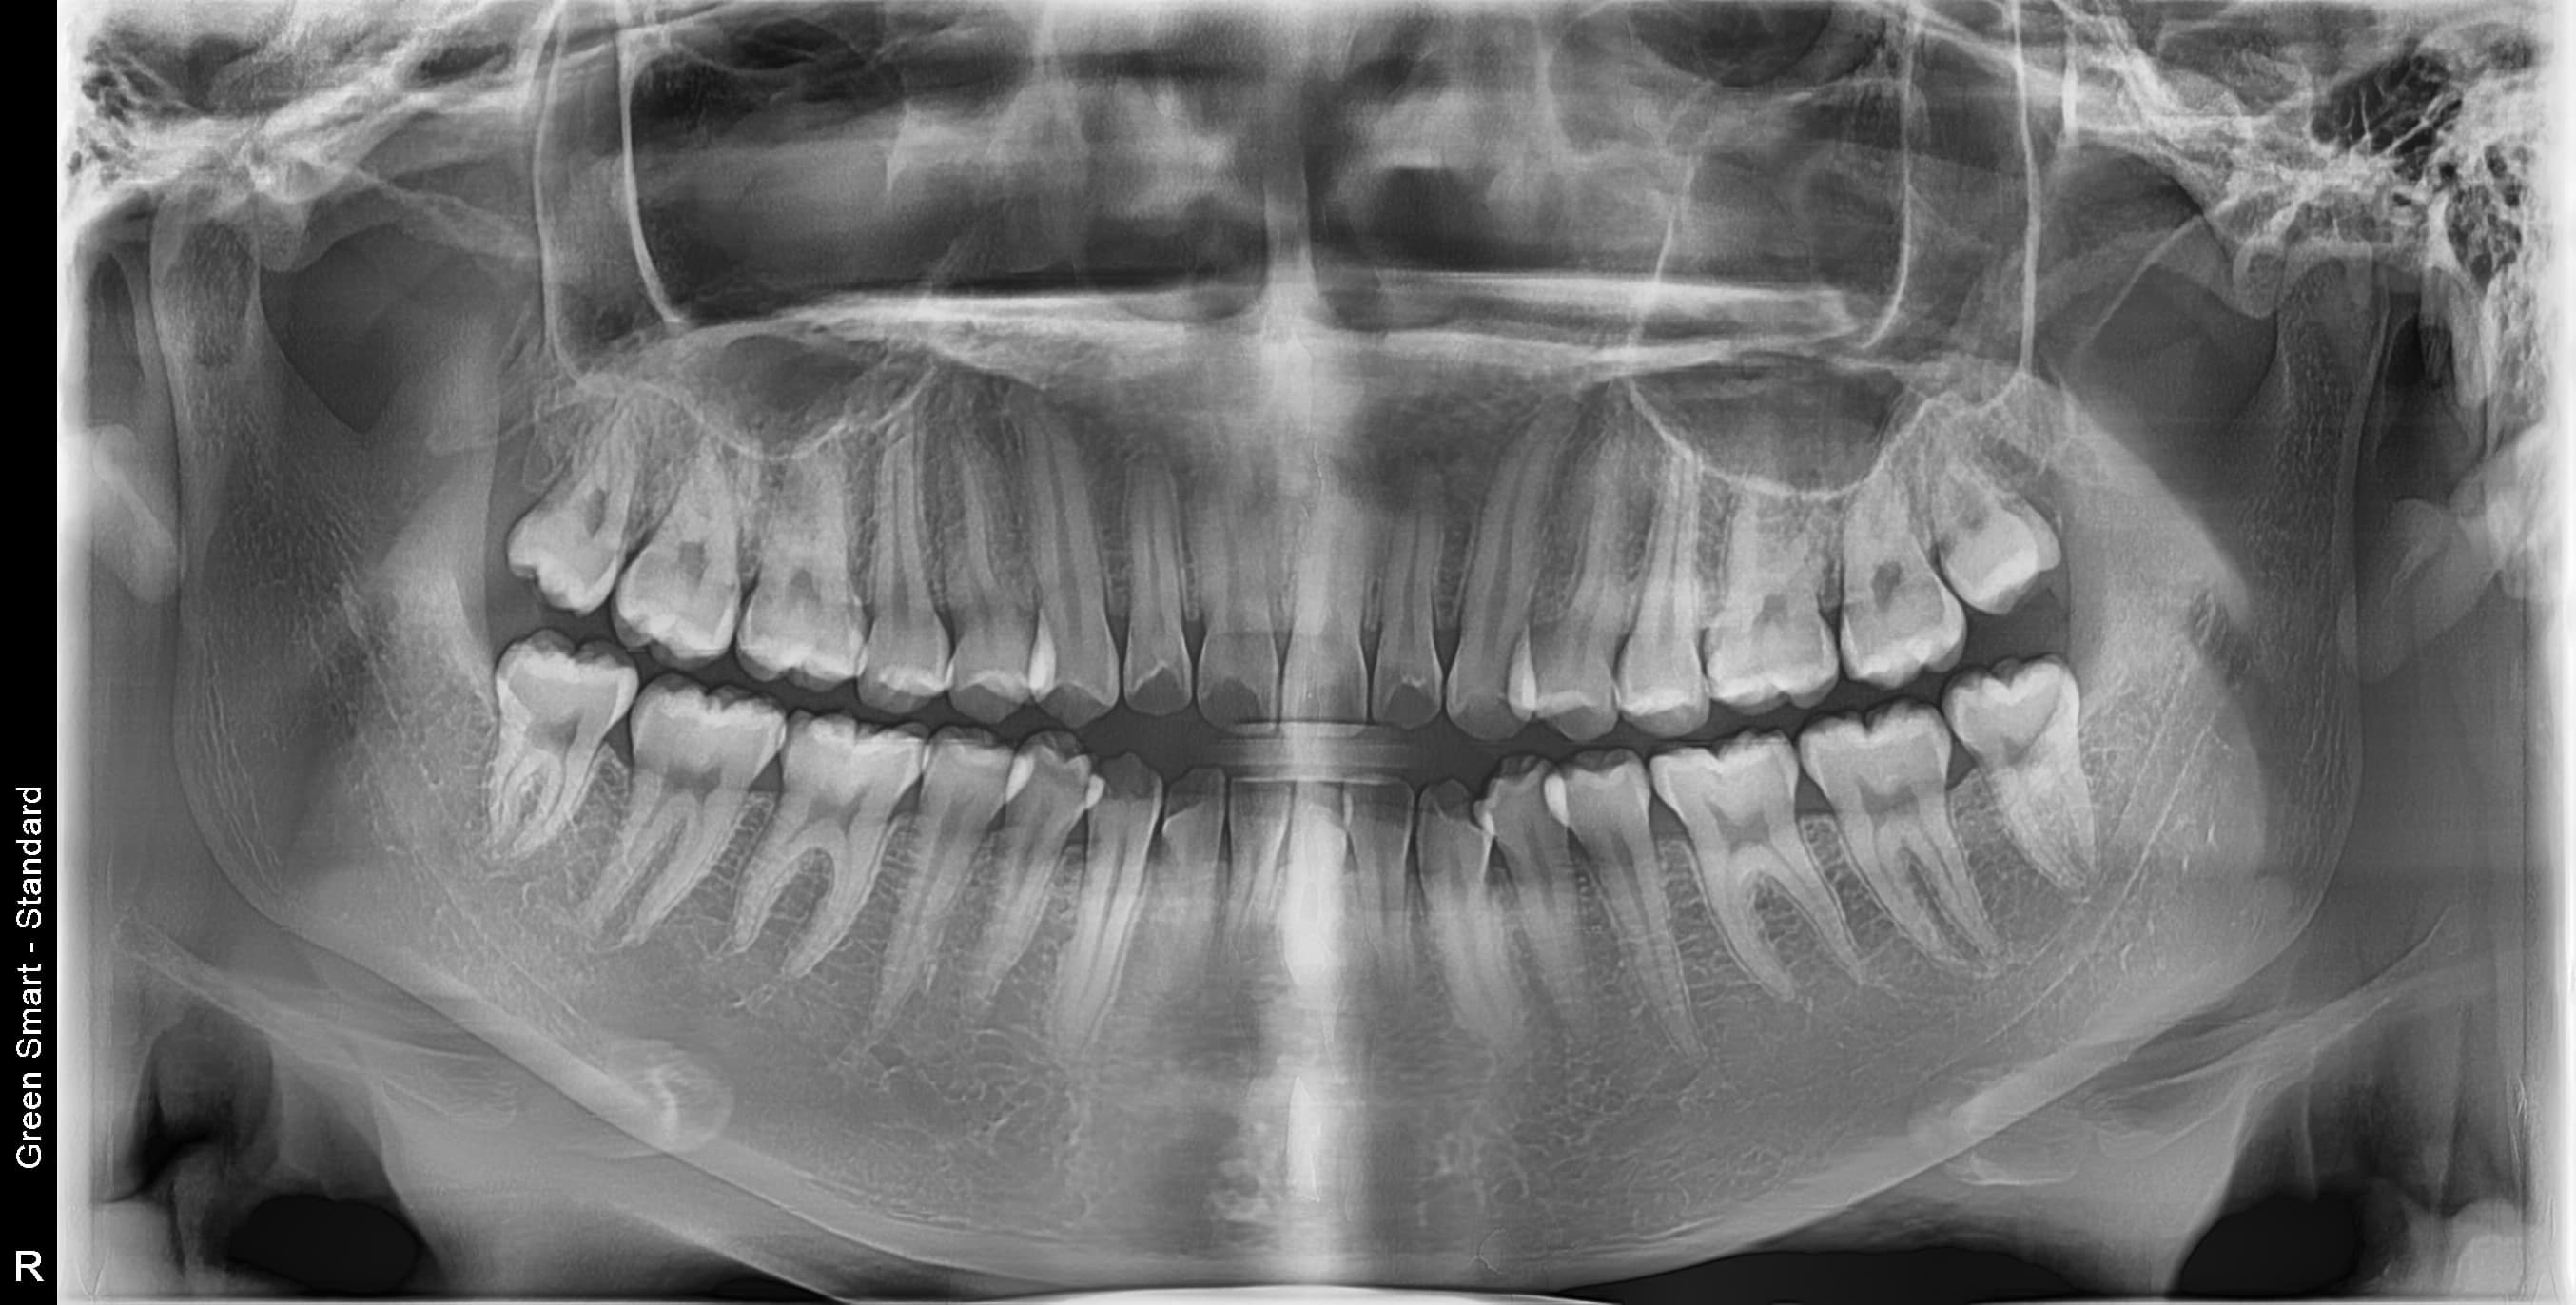

우리 병원 사랑니 발치의 특별함

2,700건 이상의 사랑니 발치 경험과 체계적인 시스템으로 차원이 다른 진료를 합니다

충분한 임상 경험

통합치의학 전문의 대표 원장의 안전하고 정확한 사랑니 발치

통증이 없어도 잇몸 속에서 염증, 충치, 치열 불균형을 일으킬 수 있습니다. 3D CT로 정밀 진단 후 필요 여부를 판단하며, 미리 뽑지 않으면 급성 염증, 인접 치아 손상, 턱관절 장애 등의 문제가 발생할 수 있습니다. 젊을수록 회복이 빠르고 합병증 위험이 적습니다.

난이도 높은 사랑니도 뽑을 수 있나요?

네, 가능합니다. 경성 메디스 치과는 2,700건 이상의 발치 경험과 대학병원급 난이도 발치가 가능한 시스템을 갖추고 있습니다. 수평매복, 완전매복 등 일반 치과에서 큰 병원을 권유하는 어려운 케이스도 3D CT 정밀 진단으로 안전하게 발치합니다.